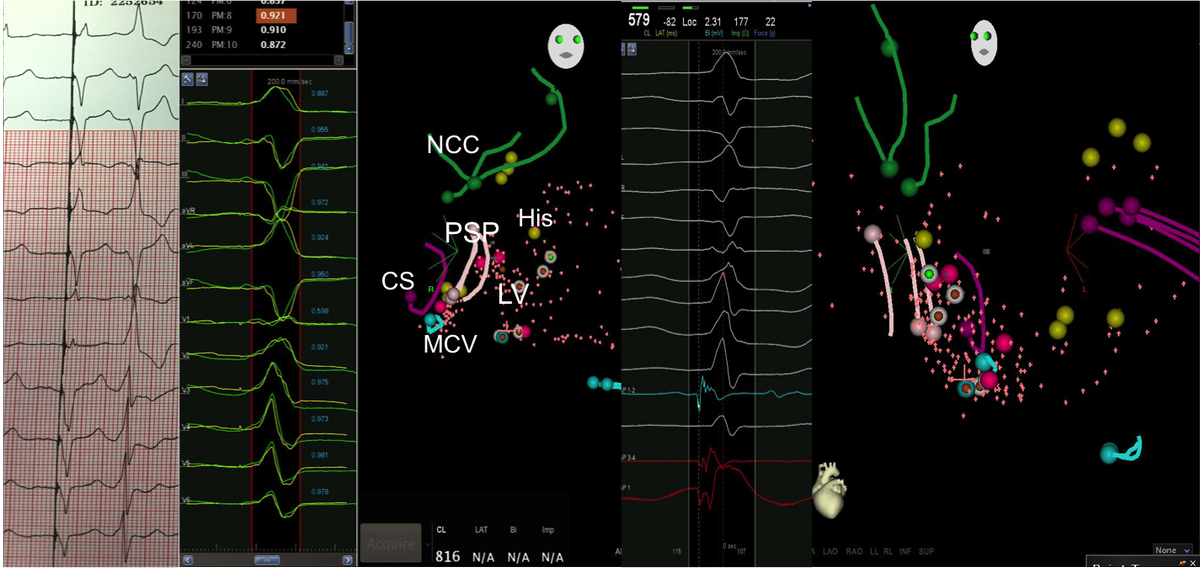

65 yo with symptomatic multifocal PVCs, ~30K, EF 45%,  3 different PVCs were ablated today..fun & require patience, thanks to the team!